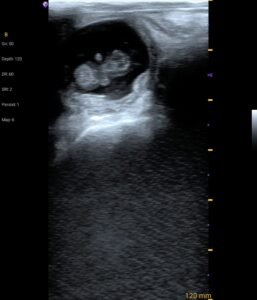

#Ganadería ¡Nieves va a ser mamá! Con el proyecto de mejoramiento genético del Gobierno de Pastaza, Nieves y otras tres vacas ya están preñadas. Antes, se invertía el doble para obtener menos resultados. Hoy, por administración directa, ahorramos casi el 50% y lograremos el doble de producción. ¡Más eficiencia, más producción para el campo ganadero de Pastaza! #ElGobiernoDelÁnimo Navegación de entradas #Desarrollo🌱 Impulsamos la producción agrícola sostenible Avanzan los trabajos de reconformación de 1.800m de la vía al balneario La Victoria,